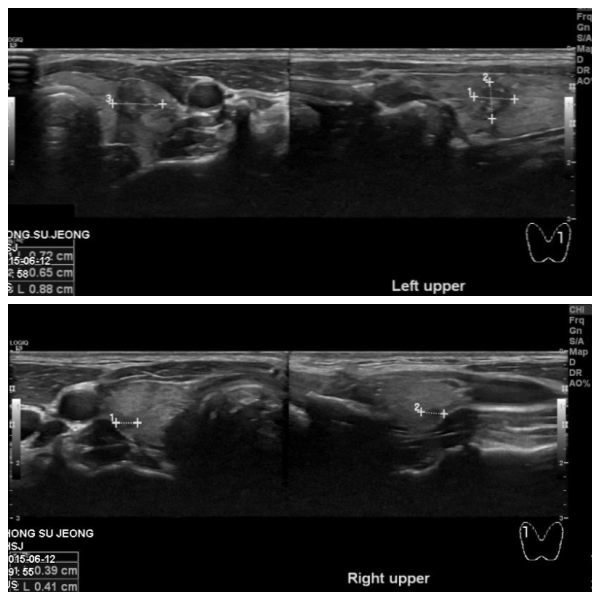

최근 목이 붓고, 피곤한 느낌이 들어 내원한  30대 여성 분으로 본원 갑상선 초음파

시행 후 양측 상엽에 의심되는 몽우리가 있어 세포검사  시행하였으며, 좌즉  갑상선

유두암 진단 되었습니다.